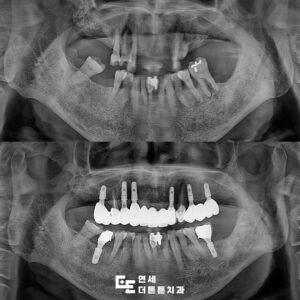

그 과정에 대해 간단히 설명을 드리면

진단 모형을 기반으로 지지 및 한계 영역을

포함한 개인 트레이를 제작하여

작업 모형을 제작한 뒤, 인공치아 배열과

교합 형성을 하여 최종적인 교합 조정까지

복잡한 과정을 거치게 됩니다.

환자분께서는 최종 틀니에

매우 만족하셨으며 저작 및 발음 기능

개선에 아주 기뻐하셨습니다.